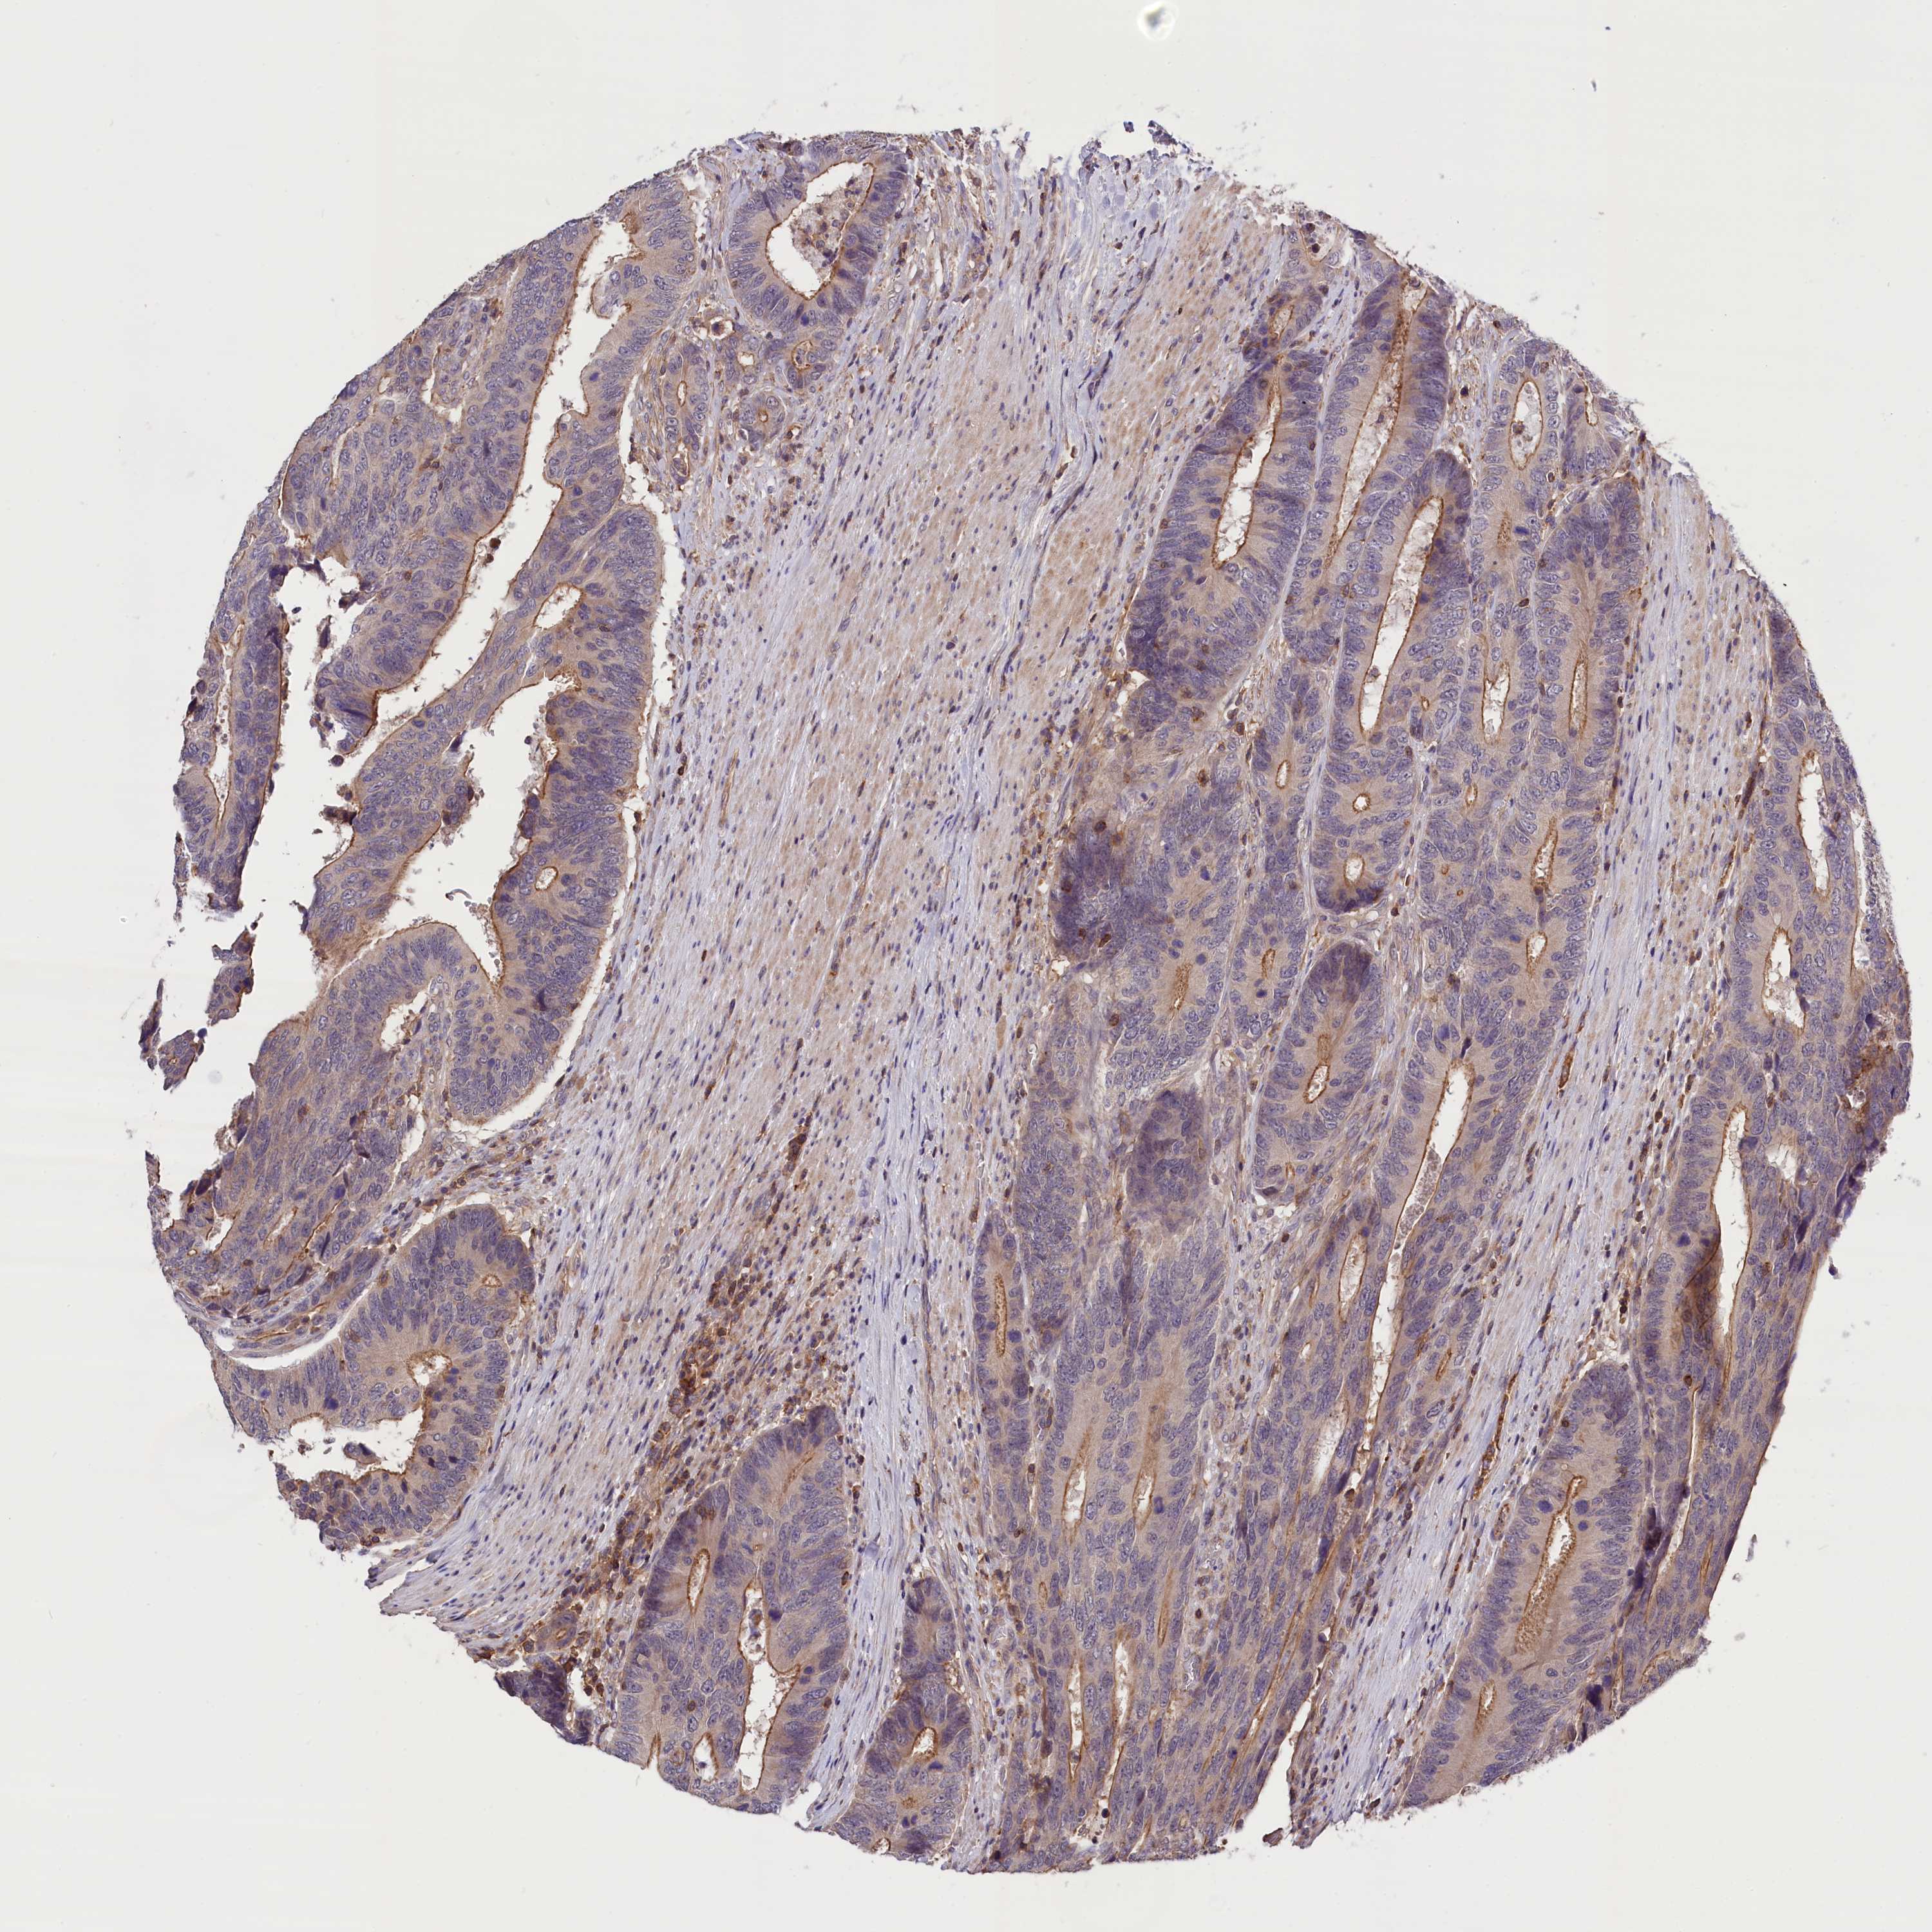

CANCER COLORECTAL CANCER Show tissue menu

Colorectal cancer

Human cancer

Colon adenocarcinoma